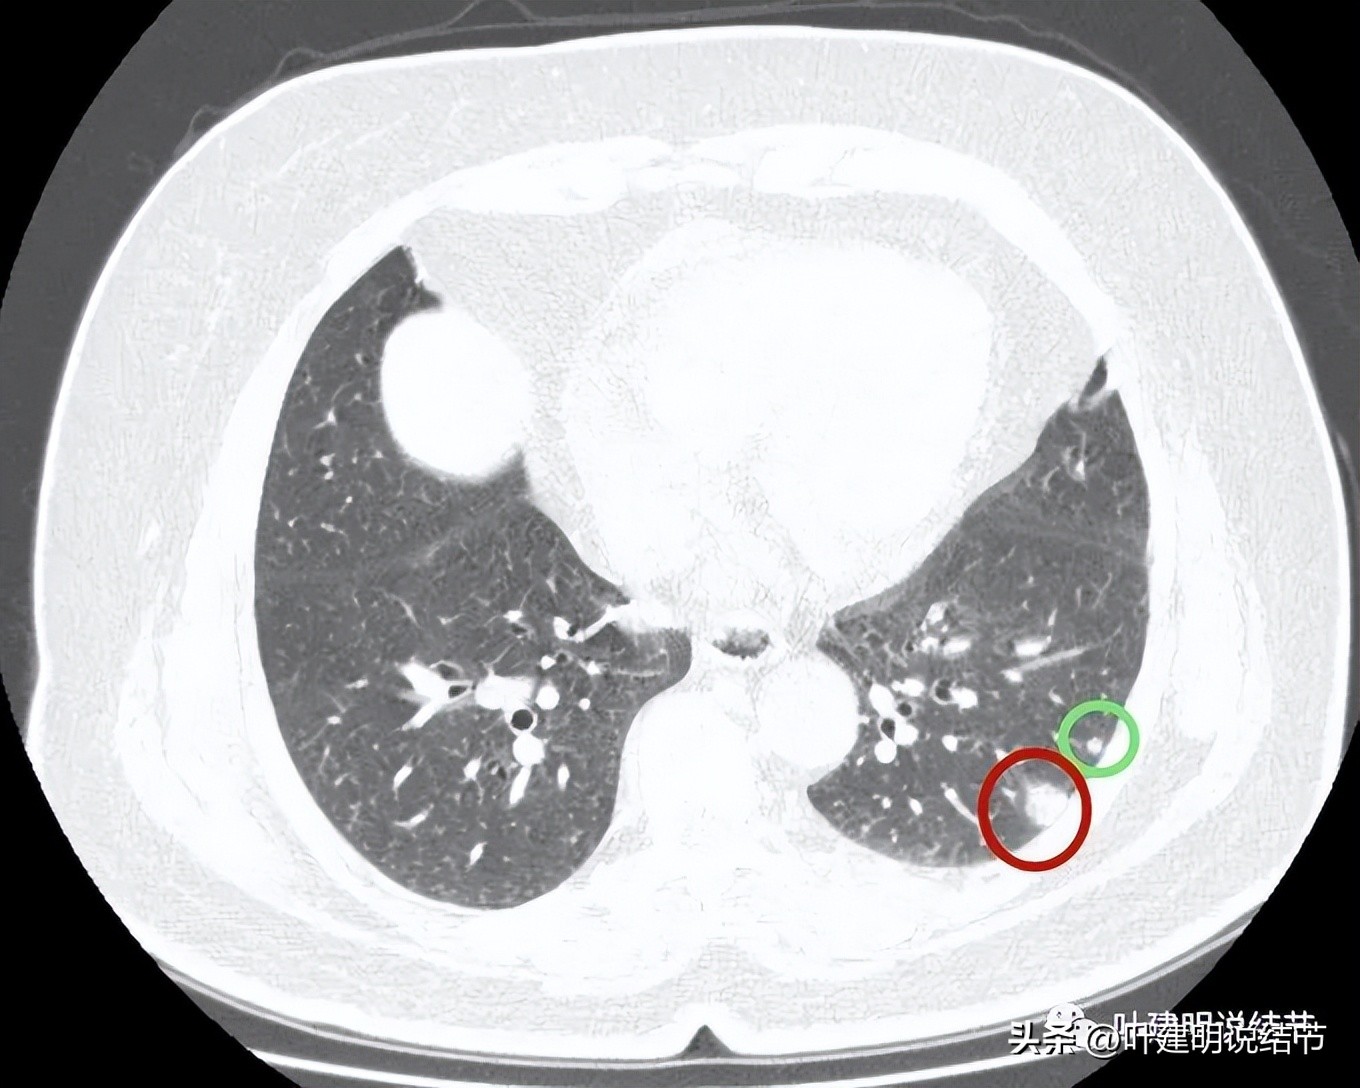

病灶3:左下叶微小实性结节,边光滑,圆形,密度高,考虑良性可能性大;

病灶4:左下叶实性结节,即主病灶,实性不是很致密的病灶,胸膜下,边界较清,邻近胸膜没有牵拉。有恶性可能性(良性的用什么疾病能解释?好像错构瘤、硬化性血管瘤、结核、肉芽肿性炎、淋巴结、急性炎症、隐球菌等常见的都靠不太上)。

病灶4:见有血管进入病灶,整体上是偏实性的,但感觉不太致密